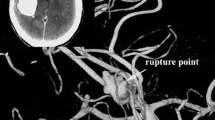

Digital images were transferred to a Macintosh workstation, and 3D vessels were reconstructed with the volume-rendering algorithm of open-source software OsiriX. The contrast leakage in each of the 5 patients could be seen as a string connecting to the aneurysm shown in Fig. 1. The skull, calcification of vessel wall, and soft tissue in the source CTA image were removed manually. Surface irregularities resulting from partial volume effects, truncated small arteries as well as other noise were also corrected manually using Amira (TGS, Inc., San Diego, CA). Table 1 displays the geometric details of the aneurysms.

2.4 Rupture points

No previous study reported the location and consequently the area of the ruptured point during contrast agent leakage. In this study, the precise point of contrast agent leakage was successfully identified from the CTA images, as shown in Fig. 1. However, the area of the rupture point is still not determined. Here, this is estimated to be 1–5% of the aneurysm surface and the corresponding surface areas are shown in Table 2. Figure 2 shows the rupture area based on this criterion. Sensitivity study on the predicted hemodynamic quantities is conducted in the latter section to explore its influence.